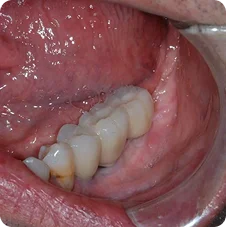

Final - Crown Placements